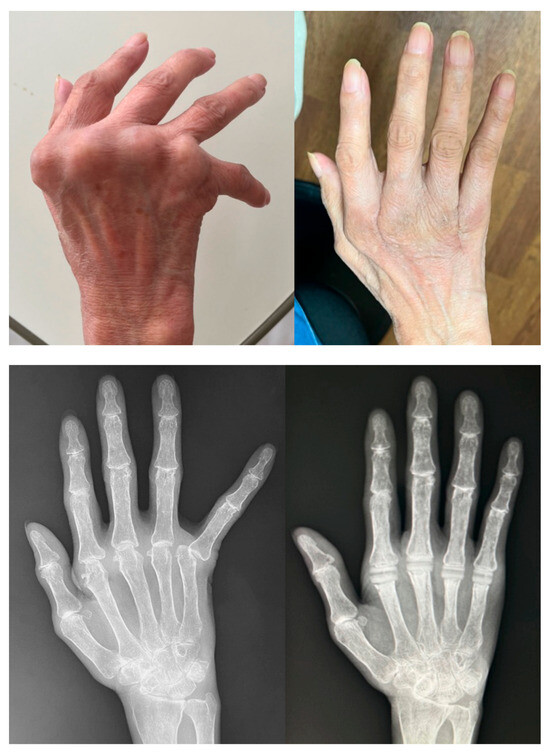

Trends in Rheumatoid Hand Surgery: Indications, Techniques, and Outcomes

by Masanori Nakayama, Yasuhiro Kiyota, Soichiro Nakamura and Mitsuru Yagi

J. Clin. Med. 2025, 14(2), 319; https://doi.org/10.3390/jcm14020319 - 7 Jan 2025

Rheumatoid arthritis (RA) causes persistent synovitis and arthritis, resulting in joint deformity and destruction throughout the body. As RA medications have evolved over the past 30 years, the surgical indications and techniques for RA joint deformities have changed. The aim of this review [...] Read more.

Rheumatoid arthritis (RA) causes persistent synovitis and arthritis, resulting in joint deformity and destruction throughout the body. As RA medications have evolved over the past 30 years, the surgical indications and techniques for RA joint deformities have changed. The aim of this review article is to summarize the recent trend of surgery for rheumatoid hand/finger deformities in previous reports and to present our recent surgical methods and outcomes for these deformities. A typical hand and finger deformity caused by RA is ulnar deviation, which is mainly caused by joint laxity and dislocation of the metacarpophalangeal joints, in addition to extensor tendon dislocation and/or wrist joint deformity. Although the incidence of hand/finger deformity and ulnar deviation caused by RA is decreasing due to advances in RA medications, patients with long-term RA or those with difficult-to-treat RA may still develop hand/finger deformity and ulnar deviation. If the hand/finger deformity is mild, it can be reduced manually, and conservative treatment with orthoses or splints may be required. If joint pain is severe despite good medical control of RA, or if the patient hopes to improve the appearance of the hand or fingers, surgical intervention is required. If there is only subluxation of the joints, which preserves their structure, reconstruction with only soft tissue surgery may be required. For example, for swan-neck deformity and boutonniére deformity, two of the most typical finger deformities due to RA, when the joint structures are almost intact and can be corrected manually, we opt for a surgical procedure that involves only soft tissue manipulation without the use of prosthetic implants. For ulnar deviation without joint destruction, we usually use a soft tissue-only surgical procedure. Our results have shown that the soft tissue-only surgery for ulnar deviation is as effective as joint replacement with implants. If the destruction of the joint has occurred and its dislocation/subluxation cannot be reduced manually, implant arthroplasty becomes necessary. If the joint destruction is severe, only intra-articular arthrodesis is required. In the era when RA can be controlled by medication, the hand surgeon should not overlook the change in the stage of the rheumatoid hand and should perform surgical intervention via the appropriate surgical method. Full article

Show Figures

Figure 1